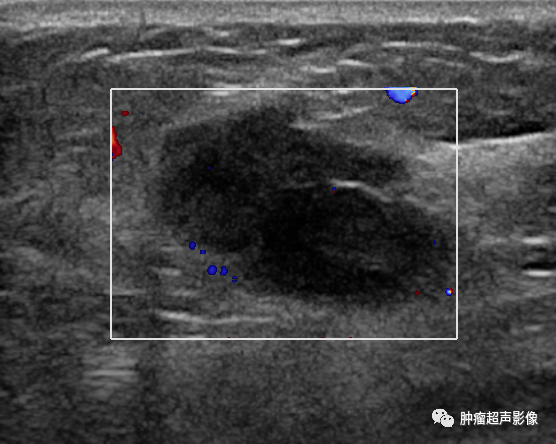

腺肌上皮腺病为乳腺腺病的一种特殊类型,非常少见,其特征为病变由增生的腺上皮和肌上皮组成,以肌上皮增生为主。如果病变形成境界明显的肿块,一般称之为腺肌...